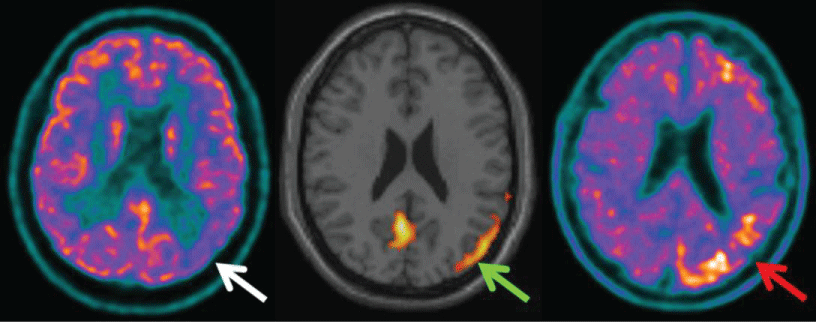

The patient underwent an 18F-FDG PET-CT scan which showed a decrease in glucidic metabolism in parietal and occipital lobes, more prominent on the left side (white arrow). The hypometabolism was confirmed also by SPM analysis (green arrow). Four months later, a PET-CT with 18F-florbetapir was performed, showing a diffuse loss of contrast between white and gray matter and, more interestingly, focal areas of increased tracer uptake in frontal and parieto-occipital cortex of the left hemisphere (red arrow).

Figure 1: PET-CT with FDG shows a decrease in glucidic metabolism in parietal and occipital lobes, more prominent on the left side (white arrow). The hypometabolism was confirmed also by SPM analysis (green arrow). PET-CT with 18F-florbetapir shows a diffuse loss of contrast between white and gray matter and, more interestingly, focal areas of increased tracer uptake in frontal and parieto-occipital cortex of the left hemisphere.